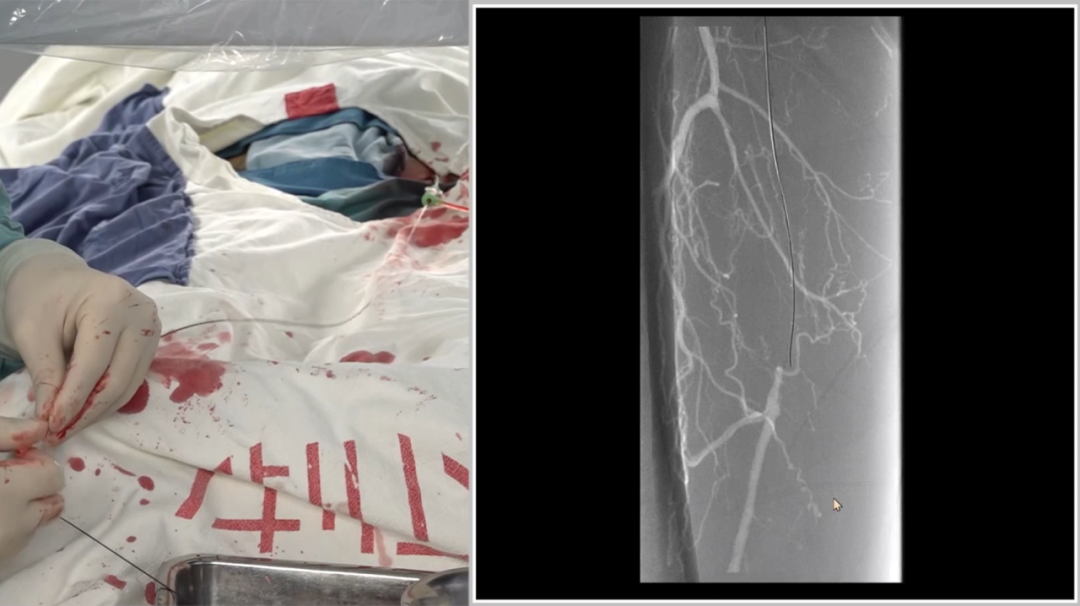

造影确认病变:长段闭塞,流出道尚可

造影显示右侧股动脉自起始段起长段闭塞,远端腘动脉及膝下动脉经股深侧枝显影,流出道条件尚可,为手术提供了基础。